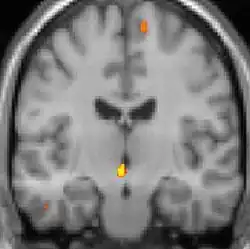

| La tomographie par émission de positons (TEP) montre les zones du cerveau étant activées durant la douleur | ||

Les images par tomographie à émission de positron indiquent les régions du cerveau qui sont activées lors de la douleur, par rapport aux périodes sans douleur. Elles montrent les régions du cerveau qui sont toujours actives durant la douleur en jaune/orange (appelé "matrice-douleur"). La zone au centre (dans les trois vues) est spécifiquement activée uniquement pendant la crise. Les photos sur la ligne du bas (effectuées par VBM) montrent les différences structurelles entre les patients souffrant d'AVF et des personnes saines : seulement une partie de l'hypothalamus est différente[50],[51].